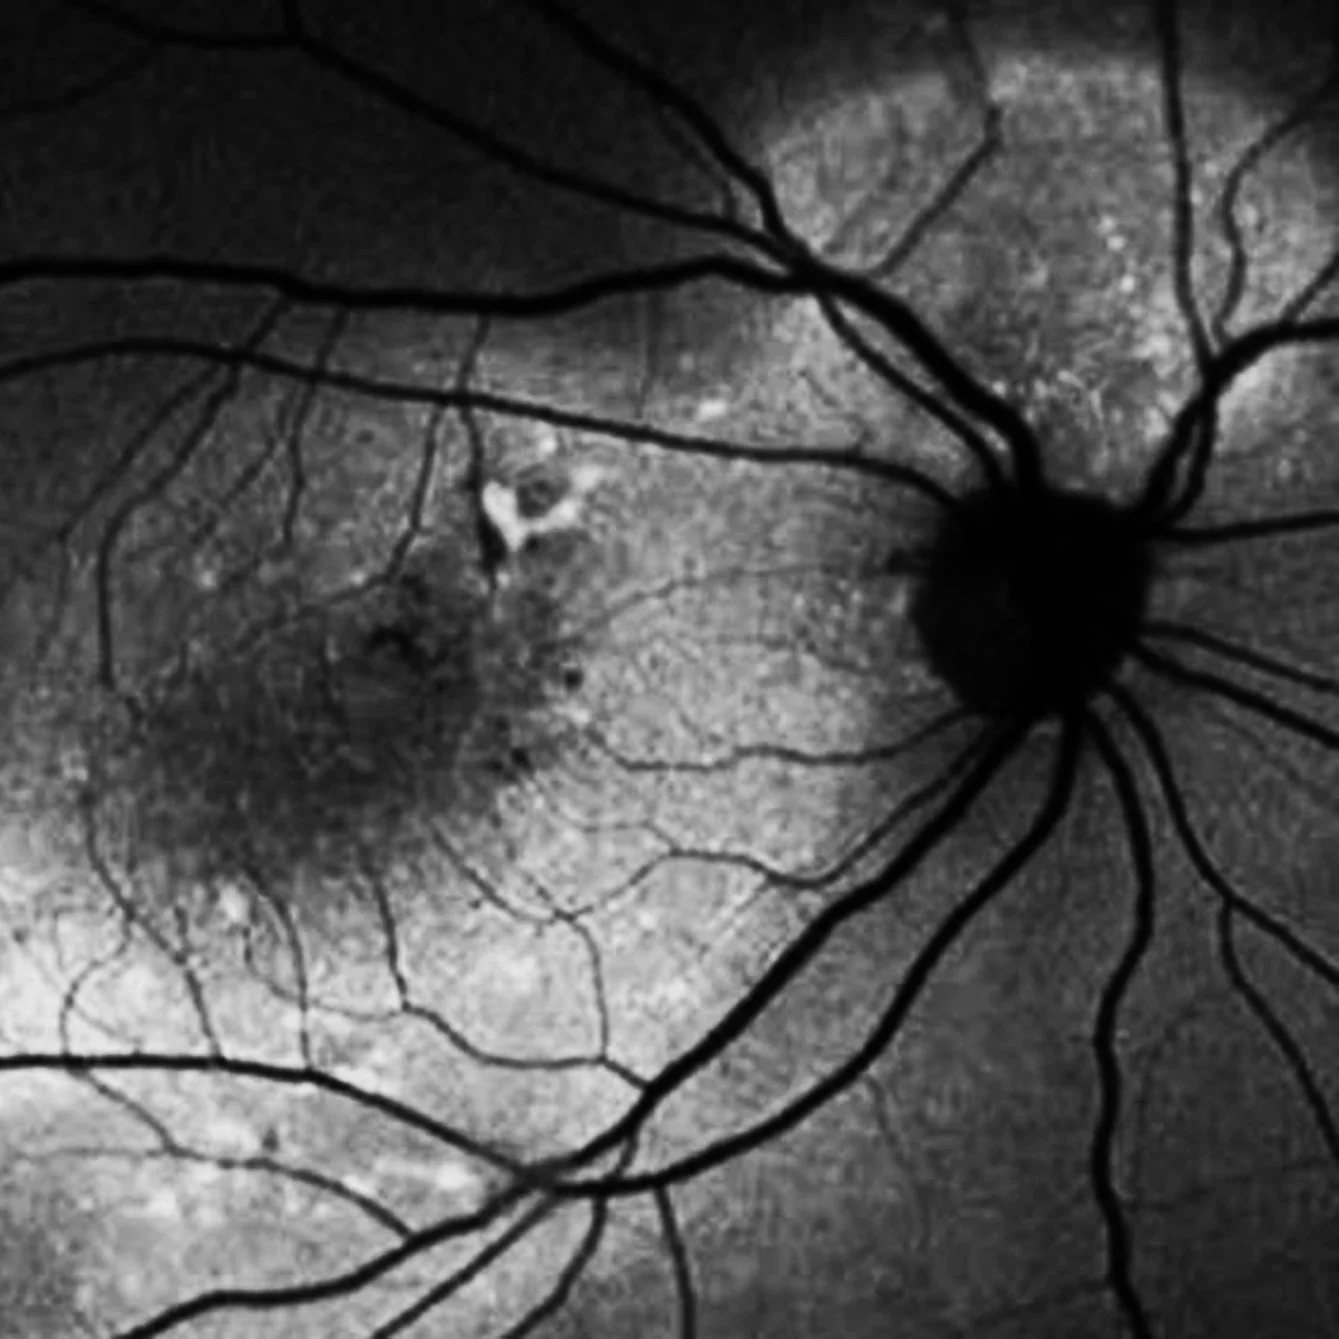

ESTUDIO DE AUTOFLUORESCENCIA

Estudio diagnóstico no invasivo útil en el diagnóstico de enfermedades que afectan el fondo de ojo (nervio y mácula)